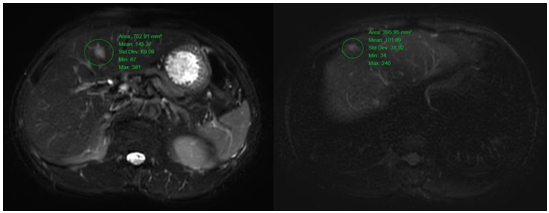

4. Hình ảnh nốt giảm tỷ trọng ở nhu mô gan hạ phân thùy IV, tăng nhẹ chuyển hóa FDG (SUVmax: 2.76). Cần phối hợp đánh giá thêm.

Hình 5. Hình ảnh các nốt tổn thương nhu mô gan hai bên tăng tín hiệu trên xung T2W cộng hưởng từ ổ bụng, hạn chế khuếch tán ở nốt hạ phân thùy V (vòng tròn màu xanh lá cây) kích thước lớn nhất ~ 14x16mm.